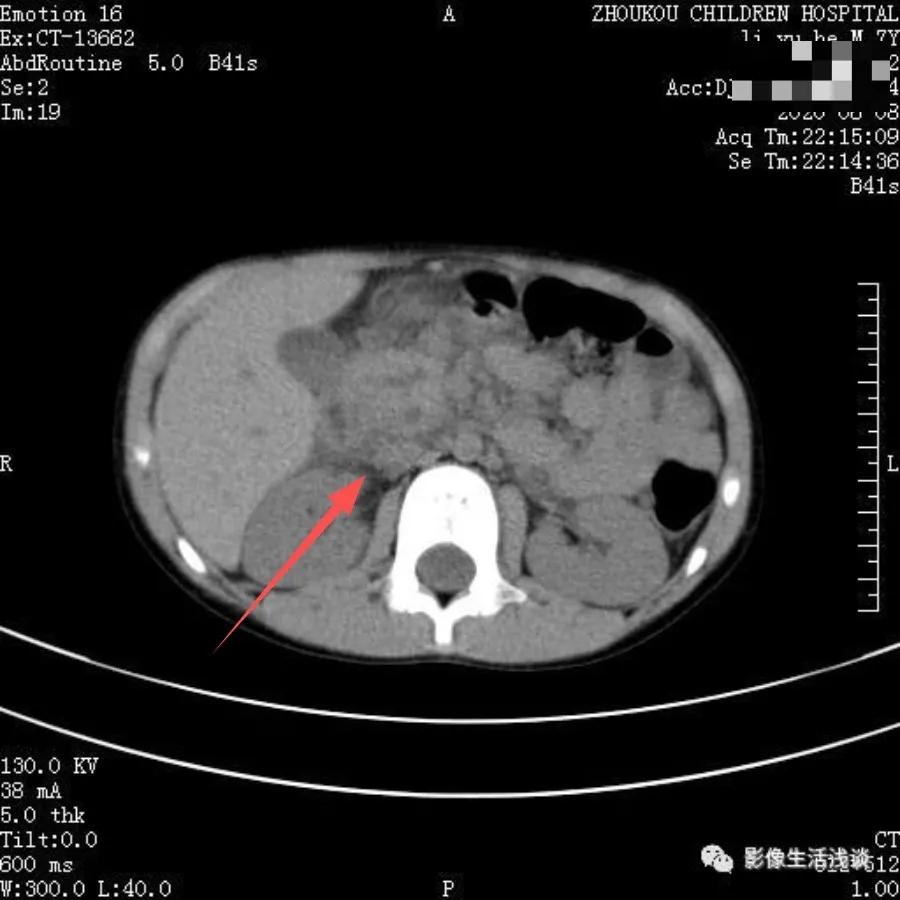

下图是一例腹痛、呕吐患者,家属以胃肠炎在诊所治疗效果不好来院检查发现胰头部体积明显肿大,其内及周围可见液性密度影,局部呈丝络样改变,考虑急性胰腺炎。